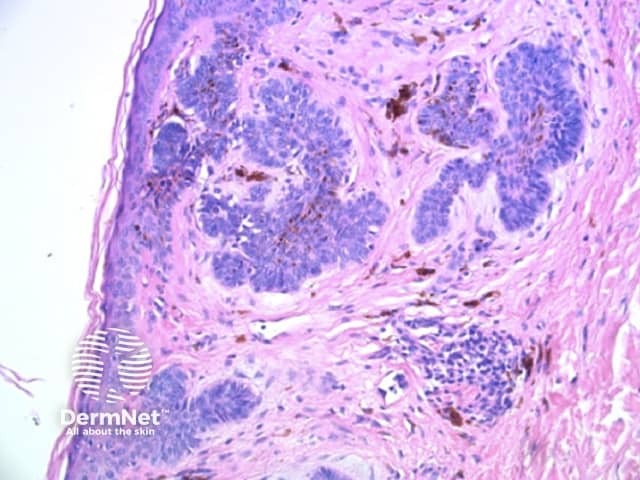

Thick lines are defined in dermatoscopy as those in which the lines are as thick, or thicker, than the spaces between them. Thick reticular or branched lines can be seen when an exuberant proliferation of pigmented melanocytes expands the epidermal rete ridges (Figure 18a,b). Thick curved lines are seen when a pigmented keratinocytic lesion produces acanthosis with thick downgrowths of pigmented epithelium as in some seborrhoeic keratoses (see previous). Thick parallel lines are discussed seperately later.

Figure 18a Figure 18b Figure 18c

Reticular and branched lines are commonly seen in association with other dermatoscopic patterns, either symmetrically or asymmetrically. The combinations with dots and clods reflects the presence of those things that cause those patterns (eg large nests of pigmented melanocytes giving clods) in conjunction with elongate pigmented rete.

The combination of dermatoscopic structureless and reticular patterns may be due to marked pigmentation of lesional cells obscuring the pattern of lines and / or loss of the epidermal rete in part of the lesion. The former can be seen centrally in some dysplastic naevi, centrally or eccentrically in combined (true and blue) naevi and eccentrically in some melanomas. The latter may be seen with epidermal remodelling in melanoma (Figure 19a,b,c), past regression of melanocytic proliferations or due to an underlying expansile dermal lesion (Figures 20-22). The colour of the structureless zone depends on the level of the pigment within the skin: it may be white, if due to dermal fibrosis; skin coloured, if associated with epidermal remodelling in association with a proliferation of non-pigmented melanocytes; and black, brown, grey or blue, if due to heavy melanin pigmentation.